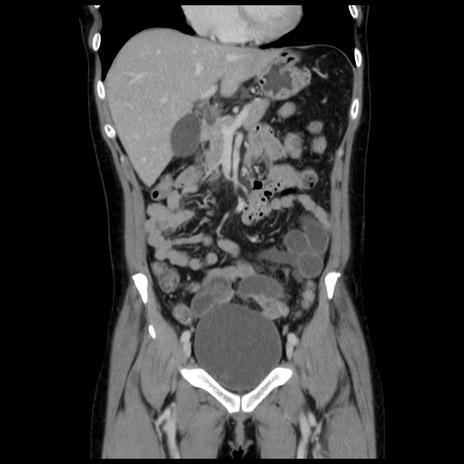

症例10(冠状断像)

【症例】 50歳代女性

【主訴】 腹痛

【現病歴】前日生レバーを食べた。今朝に排便あり。 昼前に突然発症の腹痛を生じ、当院救急外来を受診した。

【既往歴】 子宮筋腫にてで子宮全摘後

【身体所見】 意識清明、腹部:平坦、軟、下腹部やや左を中心に圧痛・反跳痛あり、筋性防御あり

【データ】WBC 7800、CRP 0.07